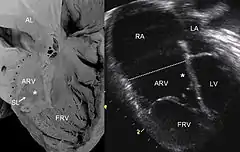

![]() Ecocardiografia de una anomalía de Ebstein: Abreviaturas: RA: aurícula derecha; LA: aurícula izquierda; ARV: ventrículo derecho atrializado; LV: ventrículo izquierdo. | ||

Se caracteriza por una alteración en el desarrollo de la válvula tricúspide que tiene una estructura y localización anómala, de tal forma que se encuentra situada en la región apical del ventrículo derecho y cumple mal su función, hasta el 50% de los pacientes presentan otras alteraciones cardíacas como comunicación interauricular. Los niños afectados sufren insuficiencia cardiaca que se manifiesta por diversos síntomas, entre ellos palpitaciones y disnea, también es frecuente la cianosis. Tiene relación a conducción anómala como Wolff-Parkinson-White.

El diagnóstico se sospecha por los síntomas y la exploración del paciente. Se confirma mediante la realización de una ecocardiografía.